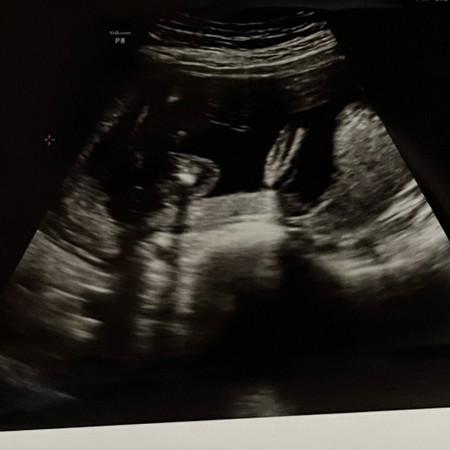

อัลตราซาวด์เพศลูก

ช่วยดูให้หน่อยค่ะ เพศชายหรือหญิงค่ะ

มีภาพอื่นที่ชัด กว่านี้ไหมคะ ดูแทบไม่ออกเลยค่ะ